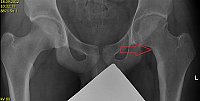

Obr. 5. Nidus osteoidního osteomu v krčku levé kyčle na RTG snímku